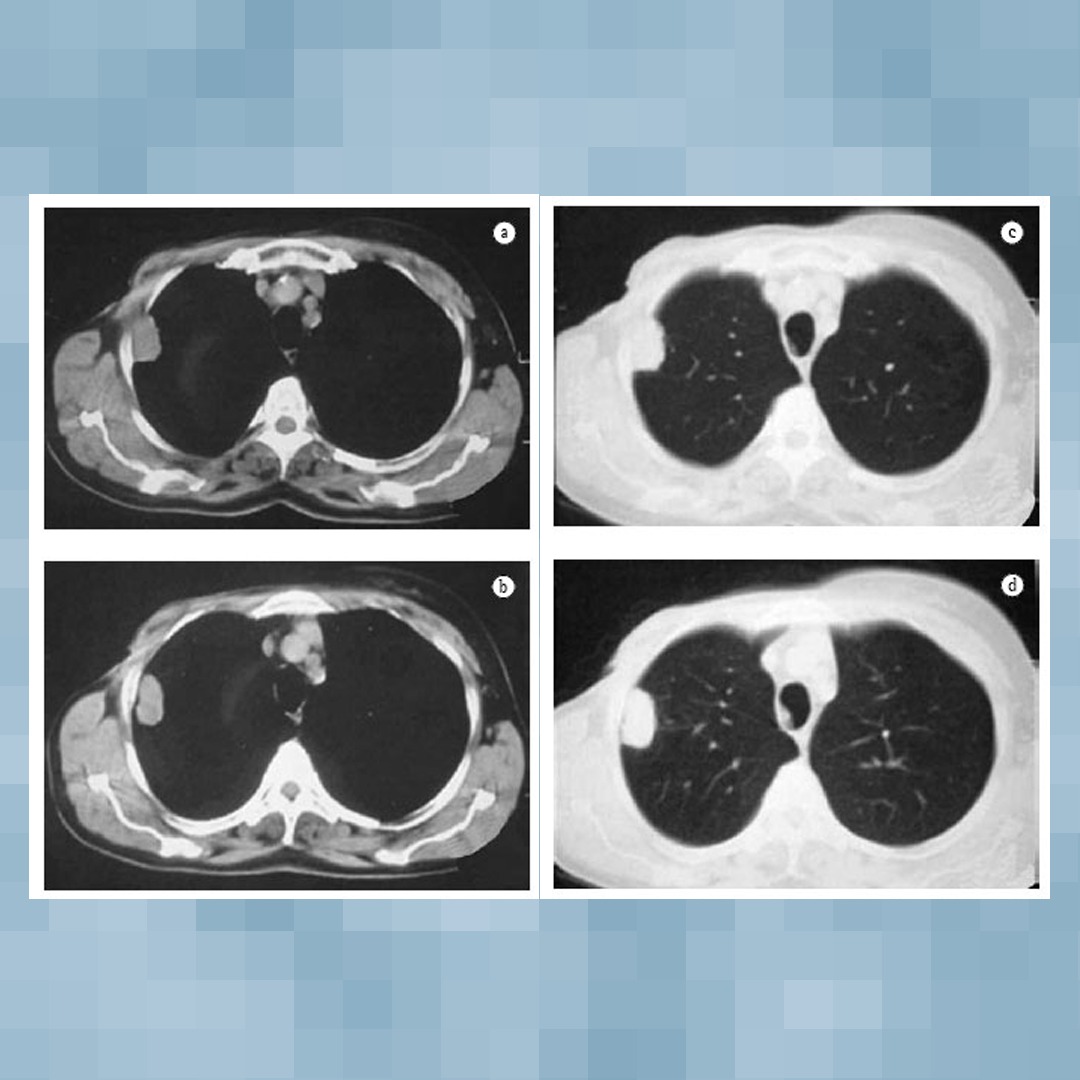

Os hamartomas são formados e revestidos pelo próprio tecido pulmonar, além de gordura e cartilagem. Em termos médicos, ele possui características bifásicas, epiteliais e mesenquimatosas. Como regra, esse tipo de tumor benigno possui o crescimento desacelerado, com o padrão de nódulo.

Os nódulos são lesões sólidas, com diâmetro maior que um milímetro e, no caso dos pulmonares, não são elevados como a maioria. Eles são muito relacionados, e até mesmo confundidos, com os cistos, que são cavidades preenchidas por líquido. Via de regra, todo nódulo pulmonar encontrado deve ser analisado para descartar a possibilidade de neoplasia maligna.

No geral, eles possuem características parecidas, sendo pequenos, calcificados e solitários. Um médico especializado sempre terá uma visão certeira do que se trata aquela anomalia, por isso se torna essencial quando qualquer tipo de tumor é encontrado.

Teste de tuberculina, ressonância magnética, imunohistologia e tomografia também são capazes de identificar esse tipo de tumor.